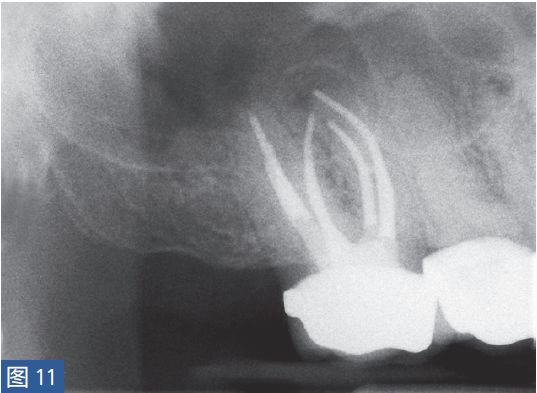

慢性根尖周脓肿(CAA chronic apical abscess)慢性根尖周脓肿(图10和11)是由长期持续的炎症引起的。脓液穿通骨和口腔黏膜,并通过口腔黏膜或上皮的瘘管流出。这些通到表皮的瘘管通常可能作为皮肤损伤而被错误处置。此外,瘘管也可能存在于牙周并通过龈沟引流。瘘管可以部分或完全地被上皮所包绕,这些上皮又被炎性结缔组织包围。临床诊断显示牙髓电活力测试结果为阴性。除非瘘管闭合,否则叩诊和触诊通常都不会引起疼痛。放射学检查,根尖周组织表现从无变化到发生明显变化。

图11:17 牙齿CAA。根管治疗12 个月后。